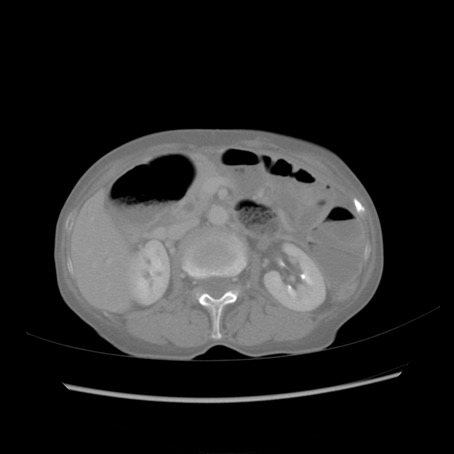

症例25(横断像)

【症例】80歳代女性

【主訴】胸のつかえ感

【現病歴】約9時間前に食後から胸のつかえた感じあり、嘔吐あり、来院。

【既往歴】胃癌(全摘)、胆摘、虫垂炎

【身体所見】心窩部に圧痛あり、反跳痛なし。

【データ】WBC 5700、CRP 0.05